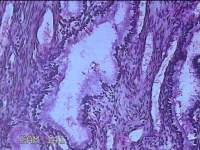

宫腔内容物

性别

女

年龄

54岁

临床诊断

1.异常子宫出血 2.围绝经期

一般病史

月经紊乱3月余,阴道流血9天。

标本名称

大体所见

灰白暗红色不规则碎组织2.5x2.2x0.7cm一堆。

图2